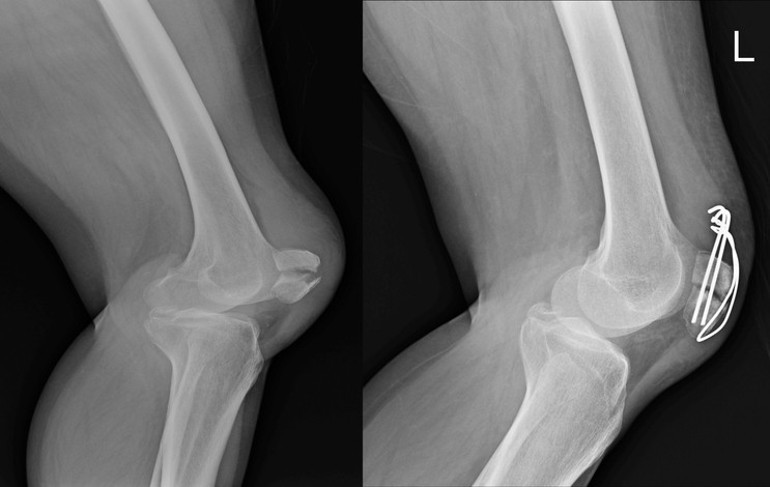

Havaalanında tekerlekli sandalye kullanarak Los Angeles'a geri döndü ve nihayet aralık ayının ortalarına doğru MR'ını çektirdi. Sonuçlar ürkütücüydü: Bacağının içinde devasa bir tümörün büyüdüğü gün gibi ortadaydı ancak MR görüntüsünde onu görmesine rağmen, bunu kendisine açıklayacak birini bulmak ve sağlığı için atması gereken sonraki adımları öğrenmek için savaşmak yine savaşmak zorunda kaldı.

İşte o zaman herkes nihayet onu ciddiye almaya başladı. Ashley'nin The Post'a anlattığına göre, MR sonuçlarına bakan doktor ona “çok büyük” bir dev hücreli bir tümöre sahip olduğuna düşündüğünü söyledi.

Ashley “Bacağımı kaybetmek istemiyordum çünkü tümör kemiğimi yiyordu. Bunu hissedebiliyordum. Kaval kemiğimi tehlikeye atıyordu ve büyümeye devam edecekti.” dedi.

Aylar sonra nihayet kendisine agresif ve milyonda bir görülen bir tümörü olduğu ve derhal alınması gerektiği, aksi takdirde içinde büyümeye devam edeceği söylendi.

Ashley, nihayet 13 Ocak'ta ağrıları başladıktan iki ay sonra tümörü çıkarmak için iki saatlik bir ameliyat geçirdi. Cerrah ayrıca kemiğinde tümörün neden olduğu çatlakları doldurmak için kemik çimentosu kullandı.

Ortopedi ve Travmatoloji Uzmanı Dr. Tarık Elma, kemiklerde görülen dev hücreli tümörlerin aslında kötü huylu kanserlerden olmadığını fakat iyi huylu tümörler olmasına rağmen bulunduğu kemikte aynen bir elma kurdunun elmayı içten kemirmesi gibi bulunduğu kemiği içten çürütmeye ve inceletmeye başladığını söyledi.

Elma, burada erken tanının çok önemli olduğunu, çünkü bazen hastalanan kemiklerdeki bu ağrılarını önemsemezse bu tümörün kemiği içten içe yiyerek zayıflatacağını ve kemiğin içini boşaltacağını, içi boşalan kemiğin de çok ufak bir darbede veya ani bir hareket sonucunda ciddi şekilde kırılabileceğinin altını çizdi. Erken tanı konması durumunda ise tedavisinin oldukça basit olduğunu ve yapılacak cerrahi müdahaleler ile tümörün temizlenerek kemiğin tekrar güçlendirilebileceğini sözlerine ekledi.